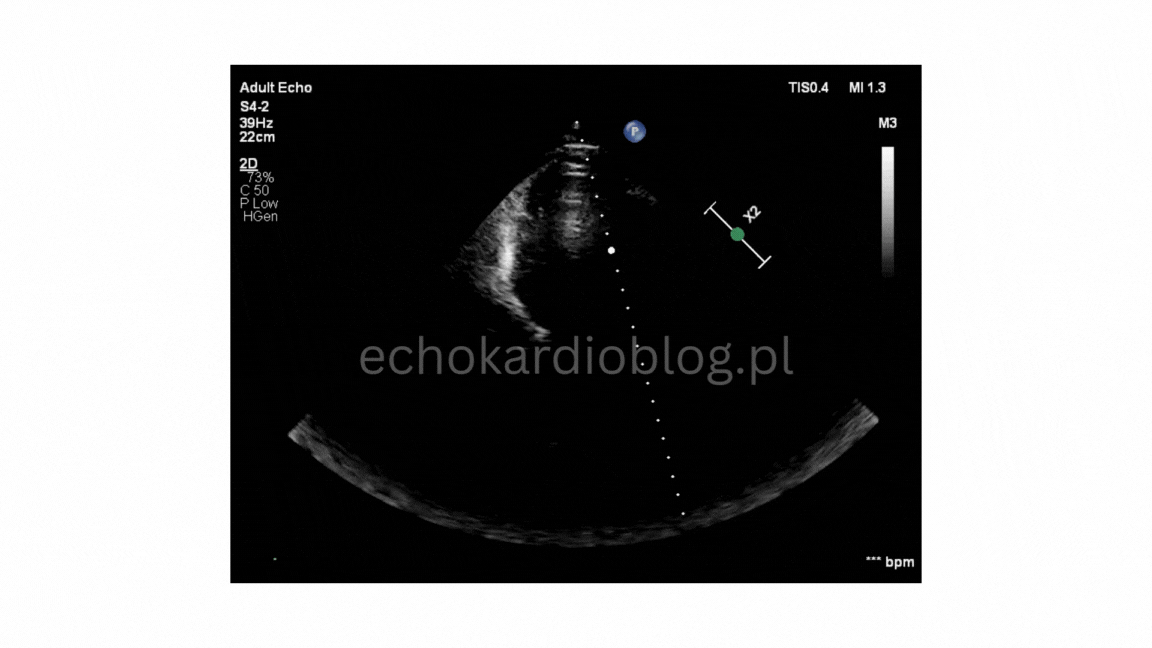

Opis przypadku: 42-letni mężczyzna, dotychczas nie leczony kardiologicznie. W załączonych obrazach

echo serca widoczny :

- nieprawidłowy ruch przegrody międzykomorowej

- ucisk prawej komory w pobliżu zastawki trójdzielnej oraz

- spłaszczenie i deformacja pierścienia trójdzielnego.

Obraz typowy dla wpływu klatki piersiowej lejkowatej na pozycję i funkcję serca.

Case description:

42-year-old man with no prior cardiac history. Echocardiography revealed :

-abnormal motion of the interventricular septum,

-compression of the right ventricule near the tricuspid valve and

-flattening with slight deformation of the valve annulus.

The findings are typical of external compression due tu pectus excavatum, affecting cardiac position and

function.